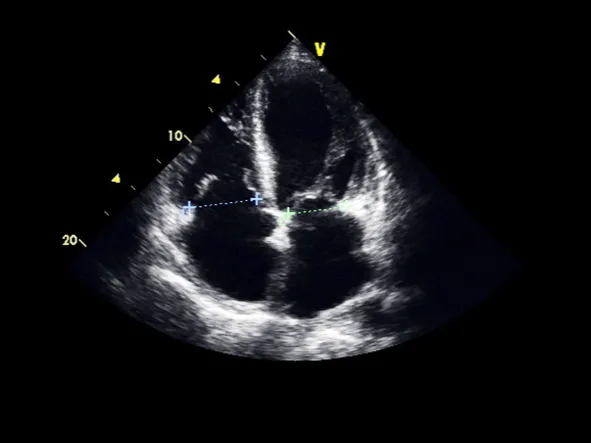

A transesophageal echocardiogram, sometimes abbreviated as a TEE, is a specialized ultrasound of the heart. It uses sound waves to generate images of the heart, as well as show the flow of blood through different areas of the heart including the heart valves. Unlike a transthoracic echocardiogram, a TEE generates the images by placing a thin probe in the esophagus while the patient is under anesthesia.

Two-dimensional (2D) echocardiogram and three-dimensional (3D) echocardiogram: These images provide pictures of the walls of the heart, the valves of the heart and large vessels that connect to the heart.

Once you are asleep, the cardiologist will insert the TEE probe in your mouth and place it into position behind the heart. At that point, images of the heart will be obtained. The TEE probe generates soundwaves, which will bounce off the heart and its structures to generate an echo. The soundwaves are identified by the machine, which then generates the 2D, 3D and Doppler images and records them.